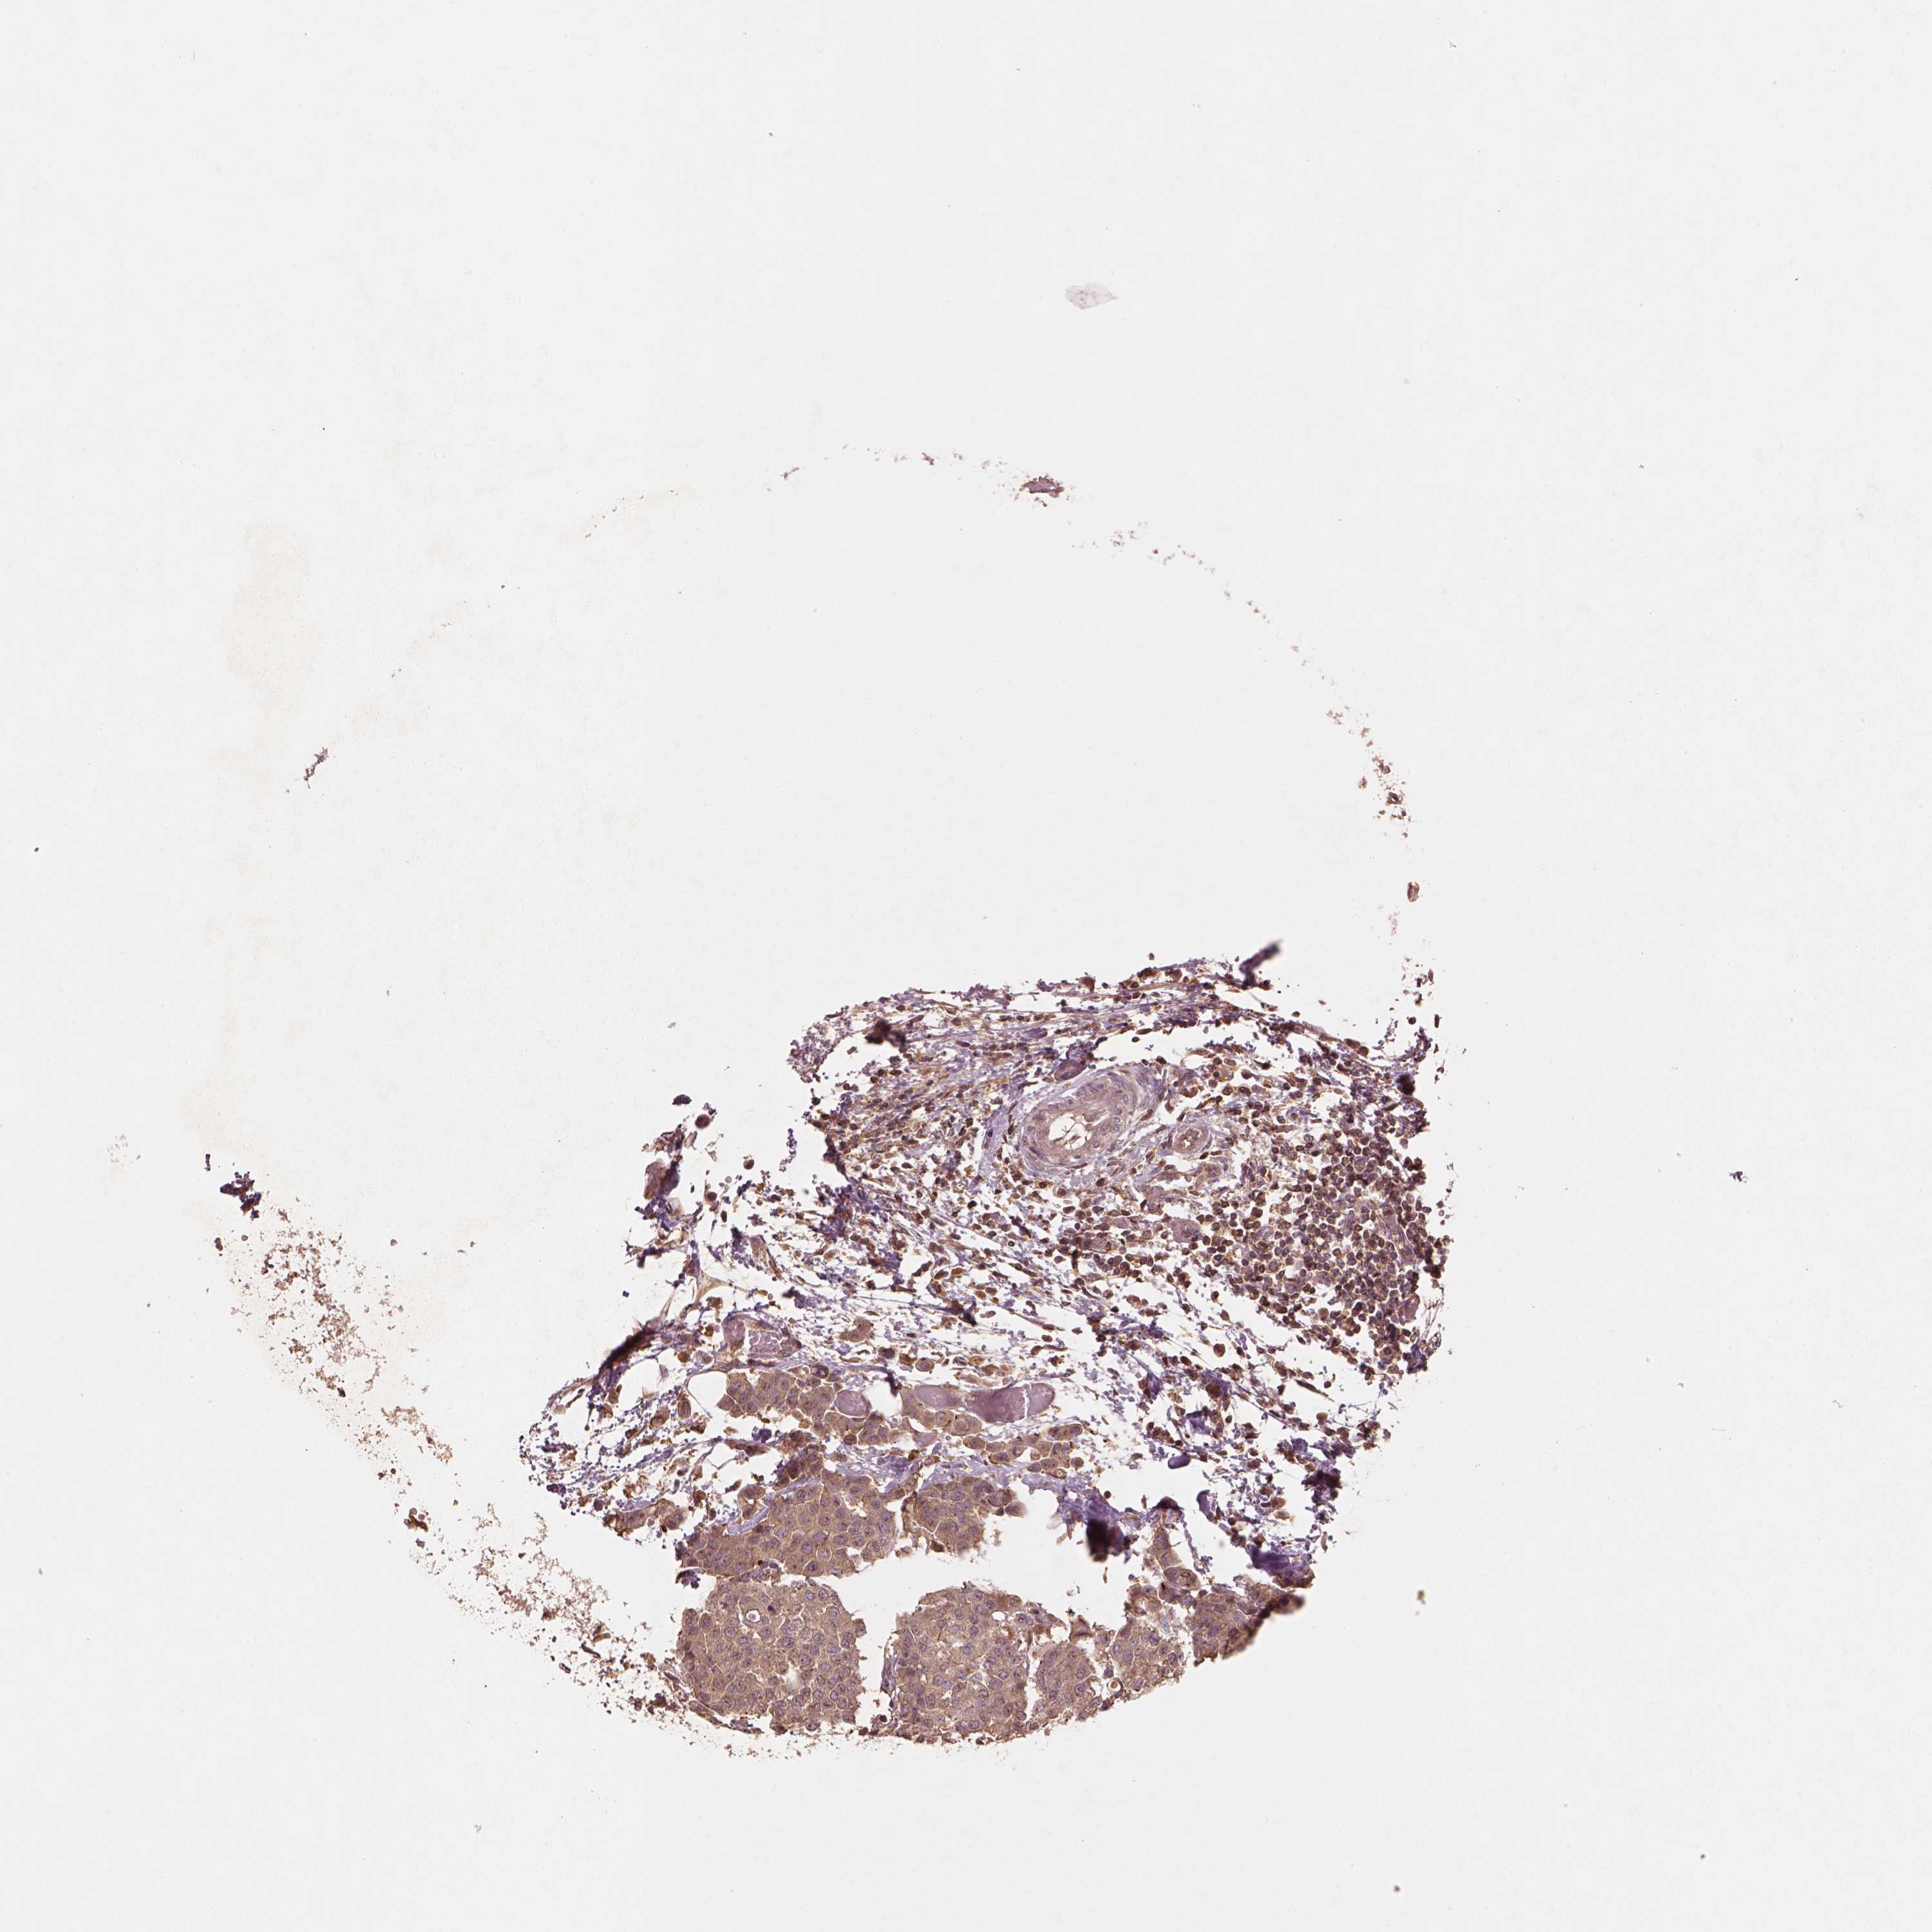

CARCINOID - Protein expressioni

A mouse-over function shows sample information and annotation data. Click on an image to view it in a full screen mode. Samples can be filtered based on level of antibody staining by selecting one or several of the following categories: high, medium, low and not detected. The assay and annotation is described here.

Antibody stainingi

Antibody staining in the annotated cell types in the current human tissue is reported as not detected, low, medium, or high, based on conventional immunohistochemistry profiling in selected tissues. This score is based on the combination of the staining intensity and fraction of stained cells.

Each image is clickable and will lead to virtual microscopy that enables deeper exploration of all samples and also displays staining intensity scores, fraction scores and subcellular localization as well as patient and tissue information for each sample.

Antibody HPA071341

Antibody CAB004602

Carcinoid, malignant, NOS